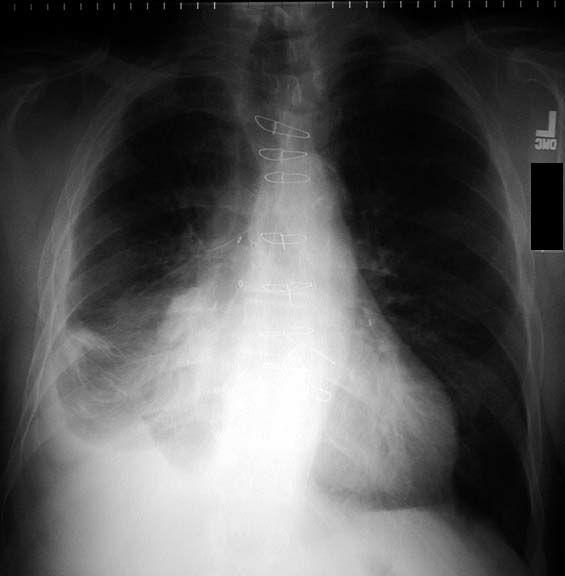

Pleural empyema wikipedia, the free encyclopedia. Pleural empyema, also known as pyothorax or purulent pleuritis, is empyema (an accumulation of pus) in the pleural cavity that can develop when bacteria invade the. Pigtail catheter use for draining pleural effusions of various. Abstract. Background. Use of smallbore pigtail catheter is a less invasive way for draining pleural effusions than chest tube thoracostomy. Methods. Pleural thickening causes symptoms, treatment of pleural. Pleural thickening symptoms are chest pain due to irritation of the pleura, shortness or difficulty of breathing, and decreased tolerance to exercise. Pleural thickening how it develops, symptoms & treatment. Pleural thickening and asbestos. Pleural thickening, also known as diffuse pleural thickening (dpt), is a lung disease in which extensive scarring thickens the pleura. Emergent management of pleural effusion overview. · a pleural effusion is an abnormal collection of fluid in the pleural space resulting from excess fluid production or decreased absorption. [1] it is the. Investigating pleural thickening the bmj. Pleural thickening who is at risk and how can they be treated? Understand what causes pleural thickening and if it is fatal. Fdg pet/ct in the management of primary pleural tumors. Objective. Fdg pet/ct is emerging as an important modality in the evaluation of pleural tumors. Pet/ct has an established role in the diagnosis and staging and.

Pleural effusion treatment & management approach. · a pleural effusion is an abnormal collection of fluid in the pleural space resulting from excess fluid production or decreased absorption or both. It is. What is apical pleural thickening? (With pictures) ehow. What is apical pleural thickening?. Apical pleural thickening refers to pleural thickening of the apical portion of the lungs. The apical portion, or apices, of the. Pleural thickening symptoms, diagnosis and. Pleural thickening treatment. Asbestoslinked pleural thickening describes the scarring and hardening of the pleura the protective membrane which surrounds your. Endometrial thickening. Causes of endometrial thickening search now! Over 85 million visitors. Emergency medicine approach to pleural effusion. · emergency medicine approach to pleural effusion 1. Approach topleural effusion = on short notice = by dr. Nawaf alamri m.D saudi board emergency medicine. Pleural thickening how it develops, symptoms &. Also try. Asbestosrelated diseases wikipedia, the free. Pleural thickening who is at risk and how can they be treated? Understand what causes pleural thickening and if it is fatal.

British medical bulletin pleural effusion medicine & health. Introduction. The accumulation of fluid in the pleural space is a common manifestation of a wide range of diseases, and frequently presents to general. What are the causes of pleural thickening?. Here you can read posts from all over the web from people who wrote about pleural thickening and pneumonia, and check the relations between pleural thickening and. Treating pleural thickening pleural thickening. Pleural thickening symptoms are chest pain due to irritation of the pleura, shortness or difficulty of breathing, and decreased tolerance to exercise. Clinical consequences of asbestosrelated diffuse pleural. · asbestosrelated diffuse pleural thickening (dpt), or extensive fibrosis of the visceral pleura secondary to asbestos exposure, is increasingly common due. Pleural thickening mesothelioma cancer. Also try. Pleural effusion characterization with ct attenuation. Abstract objective. The purpose of this study was to assess the utility of ct in characterizing pleural effusions on the basis of attenuation values and ct appearance. Pleural thickening causes symptoms, treatment of. Pleural thickening and asbestos. Pleural thickening, also known as diffuse pleural thickening (dpt), is a lung disease in which extensive scarring thickens the pleura.